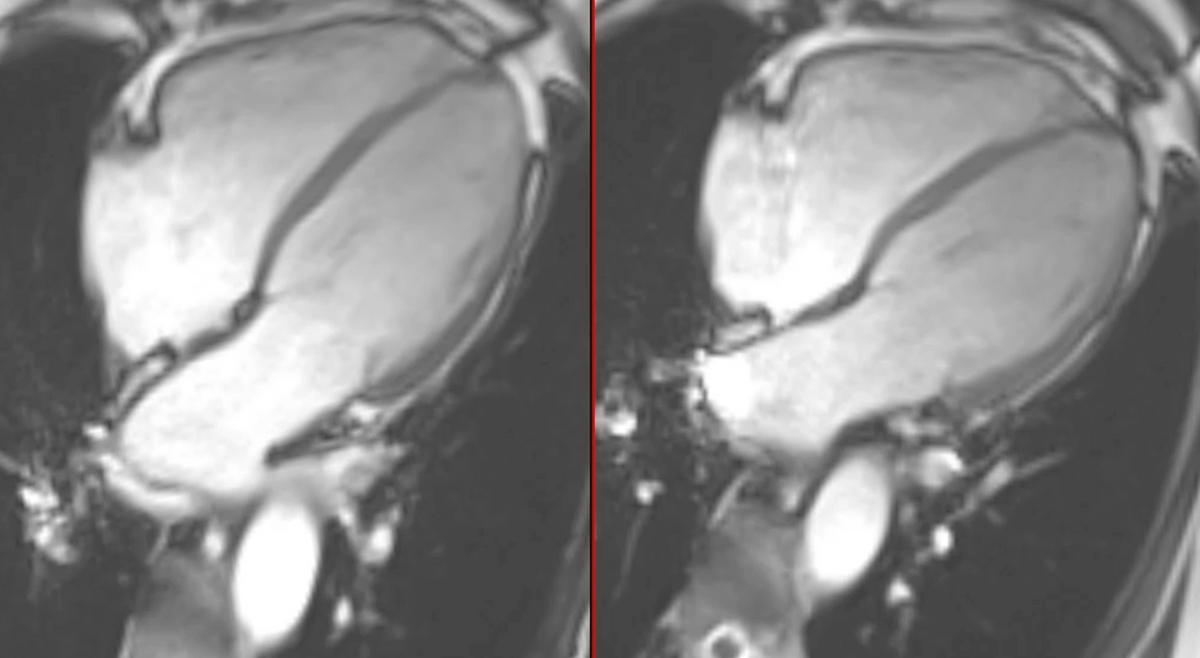

Atrial myopathy